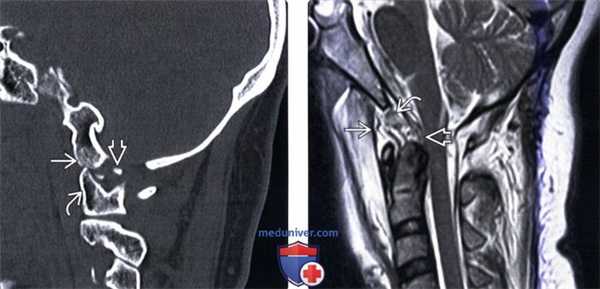

(Слева) Этот сагиттальный КТ-срез иллюстрирует передний подвывих мыщелка затылочной кости относительно С1. Видны свободно лежащие небольшие фрагменты мыщелка.

(Справа) Т2-ВИ, сагиттальная проекция: выраженные изменения связочного аппарата КВС, истончение и нарушение непрерывности текториальной мембраны. Передняя атланто-затылочная мембрана неправильной формы и натянута кпереди. Аномальный гипоинтенсивный сигнал от мягких тканей в надзубовидной области позволяет заподозрить повреждение апикальной, крыловидной и связки Баркова.